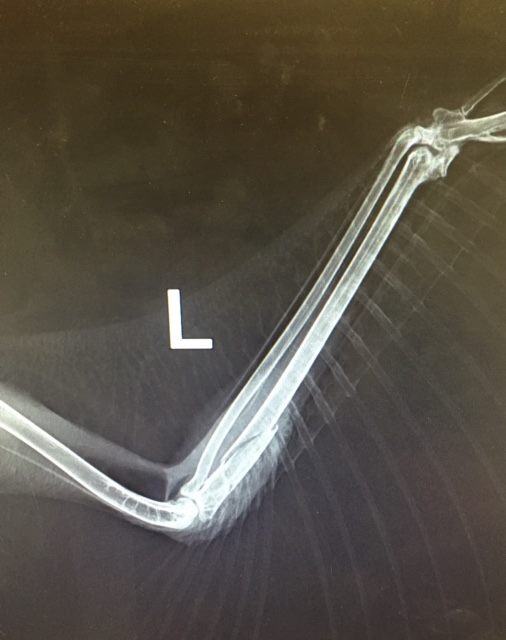

The owl was whisked to the Animal Clinic of Regina, which confirmed a fractured wing.

And treated the injury.